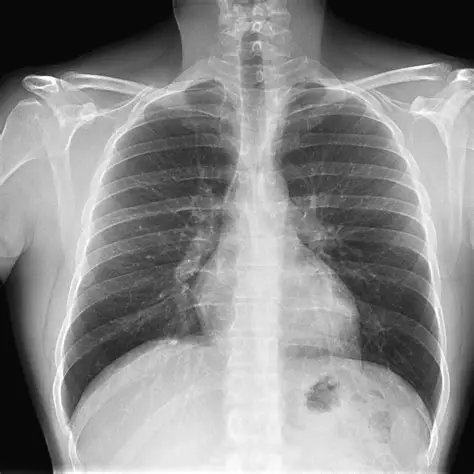

Avaliar os pulmões, coração, vasos sanguíneos, ossos torácicos e diafragma.

A leitura do RX de tórax deve ser sistemática, seguindo estruturas anatômicas. Aqui está um modelo prático:

A – Avaliação geral

Técnica adequada (posição, penetração, inspiração)

Simetria da imagem

Presença de artefatos

B – Pulmões e brônquios

Transparência normal (sem opacidades)

Presença de infiltrados, nódulos, cavidades ou consolidações

Linhas pleurais (espessamento, derrames)

C – Coração e mediastino

Avaliar o índice cardiotorácico (diâmetro cardíaco ≤ 50% do tórax)

Contornos cardíacos regulares

Alargamento do mediastino pode indicar aneurisma, linfadenopatia, etc.

D – Vasos sanguíneos

Hilo pulmonar e vasos pulmonares visíveis

Congestão vascular (pode indicar insuficiência cardíaca)

E – Estruturas ósseas

Costelas, clavículas, vértebras

Fraturas, lesões líticas, desalinhamentos

F – Diafragma e espaço pleural

Cúpulas diafragmáticas simétricas

Presença de ar (pneumotórax) ou líquido (derrame pleural)

Sinais de hérnia diafragmática ou elevação